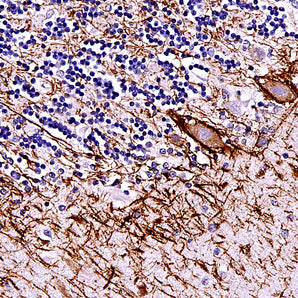

Mouse Monoclonal Antibodies